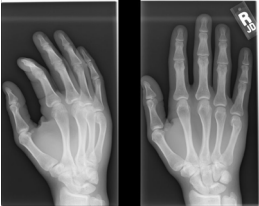

26 年輕男性患者主訴右手疼痛,昨日打球跌倒引起,患部 X 光檢查如附圖,下列相關敘述何者正確? ①此類型骨折係由外力沿掌骨縱軸作用在掌骨頭所致 ②患部局部腫脹疼痛,可能觸及骨擦音及畸形 ③此骨折稱為巴氏(Barton)骨折 ④骨折斷端因骨間肌及屈指肌的牽拉而呈現成角畸形

(A)①②③ (B)①②④ (C)①③④ (D)②③④